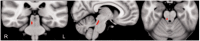

Freezing of gait is one of the most debilitating symptoms in Parkinson's disease as it causes falls and reduces mobility and quality of life. The pedunculopontine nucleus is one of the major nuclei of the mesencephalic locomotor region and has neurons related to anticipatory postural adjustments preceding step initiation as well as to the step itself, thus it may be critical for coupling posture and gait to avoid freezing. Because freezing of gait and postural impairments have been related to frontal lesions and frontal dysfunction such as executive function, we hypothesized that freezing is associated with disrupted connectivity between midbrain locomotor regions and medial frontal cortex. We used diffusion tensor imaging to quantify structural connectivity of the pedunculopontine nucleus in patients with Parkinson's disease with freezing of gait, without freezing, and healthy age-matched controls. We also included behavioural tasks to gauge severity of freezing of gait, quantify gait metrics, and assess executive cognitive functions to determine whether between-group differences in executive dysfunction were related to pedunculopontine nucleus structural network connectivity. Using seed regions from the pedunculopontine nucleus, we were able to delineate white matter connections between the spinal cord, cerebellum, pedunculopontine nucleus, subcortical and frontal/prefrontal cortical regions. The current study is the first to demonstrate differences in structural connectivity of the identified locomotor pathway in patients with freezing of gait. We report reduced connectivity of the pedunculopontine nucleus with the cerebellum, thalamus and multiple regions of the frontal cortex. Moreover, these structural differences were observed solely in the right hemisphere of patients with freezing of gait. Finally, we show that the more left hemisphere-lateralized the pedunculopontine nucleus tract volume, the poorer the performance on cognitive tasks requiring the initiation of appropriate actions and/or the inhibition of inappropriate actions, specifically within patients with freezing. These results support the notion that freezing of gait is strongly related to structural deficits in the right hemisphere's locomotor network involving prefrontal cortical areas involved in executive inhibition function.